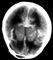

Решающее значение в диагностике субарахноидального кровоизлияния имеет обнаружение крови в цереброспинальной жидкости при люмбальной пункции. В острой фазе кровоизлияния при микроскопическом исследовании цереброспинальной жидкости в ней обнаруживаются форменные элементы крови в таком же соотношении, как и в периферической крови. В дальнейшем определяется нейтрофильный, а затем лимфоцитарный плеоцитоз. Через 3—4 дня после кровоизлияния цереброспинальная жидкость становится ксантохромной. Необходимо учитывать, что кровь в цереброспинальной жидкости может появиться в результате повреждения кровеносного сосуда при люмбальной пункции (так называемая путевая кровь). В сомнительных случаях целесообразно центрифугировать кровянистую цереброспинальную жидкость. При «путевом» кровотечении после центрифугирования надосадочная жидкость остается прозрачной, а при субарахноидальном кровоизлиянии — она ксантохромная. Убедительные данные для подтверждения подоболочечных кровоизлияний могут ныть получены с помощью компьютерной томографии, при которой обнаруживается кровь, скопившаяся субдурально (рис. 1) или в базальных цистернах мозга и субарахноидальных щелях (рис. 2). С этой же целью может быть использована ядерно-магнитно-резонансная томография. Оба метода позволяют обнаружить гематому, расположенную в субарахноидальном или субдуральном пространстве, а также смещение мозга, обусловленное гематомой. Смещение мозга при подоболочечных гематомах может быть выявлено и с помощью эхоэнцефалографии.